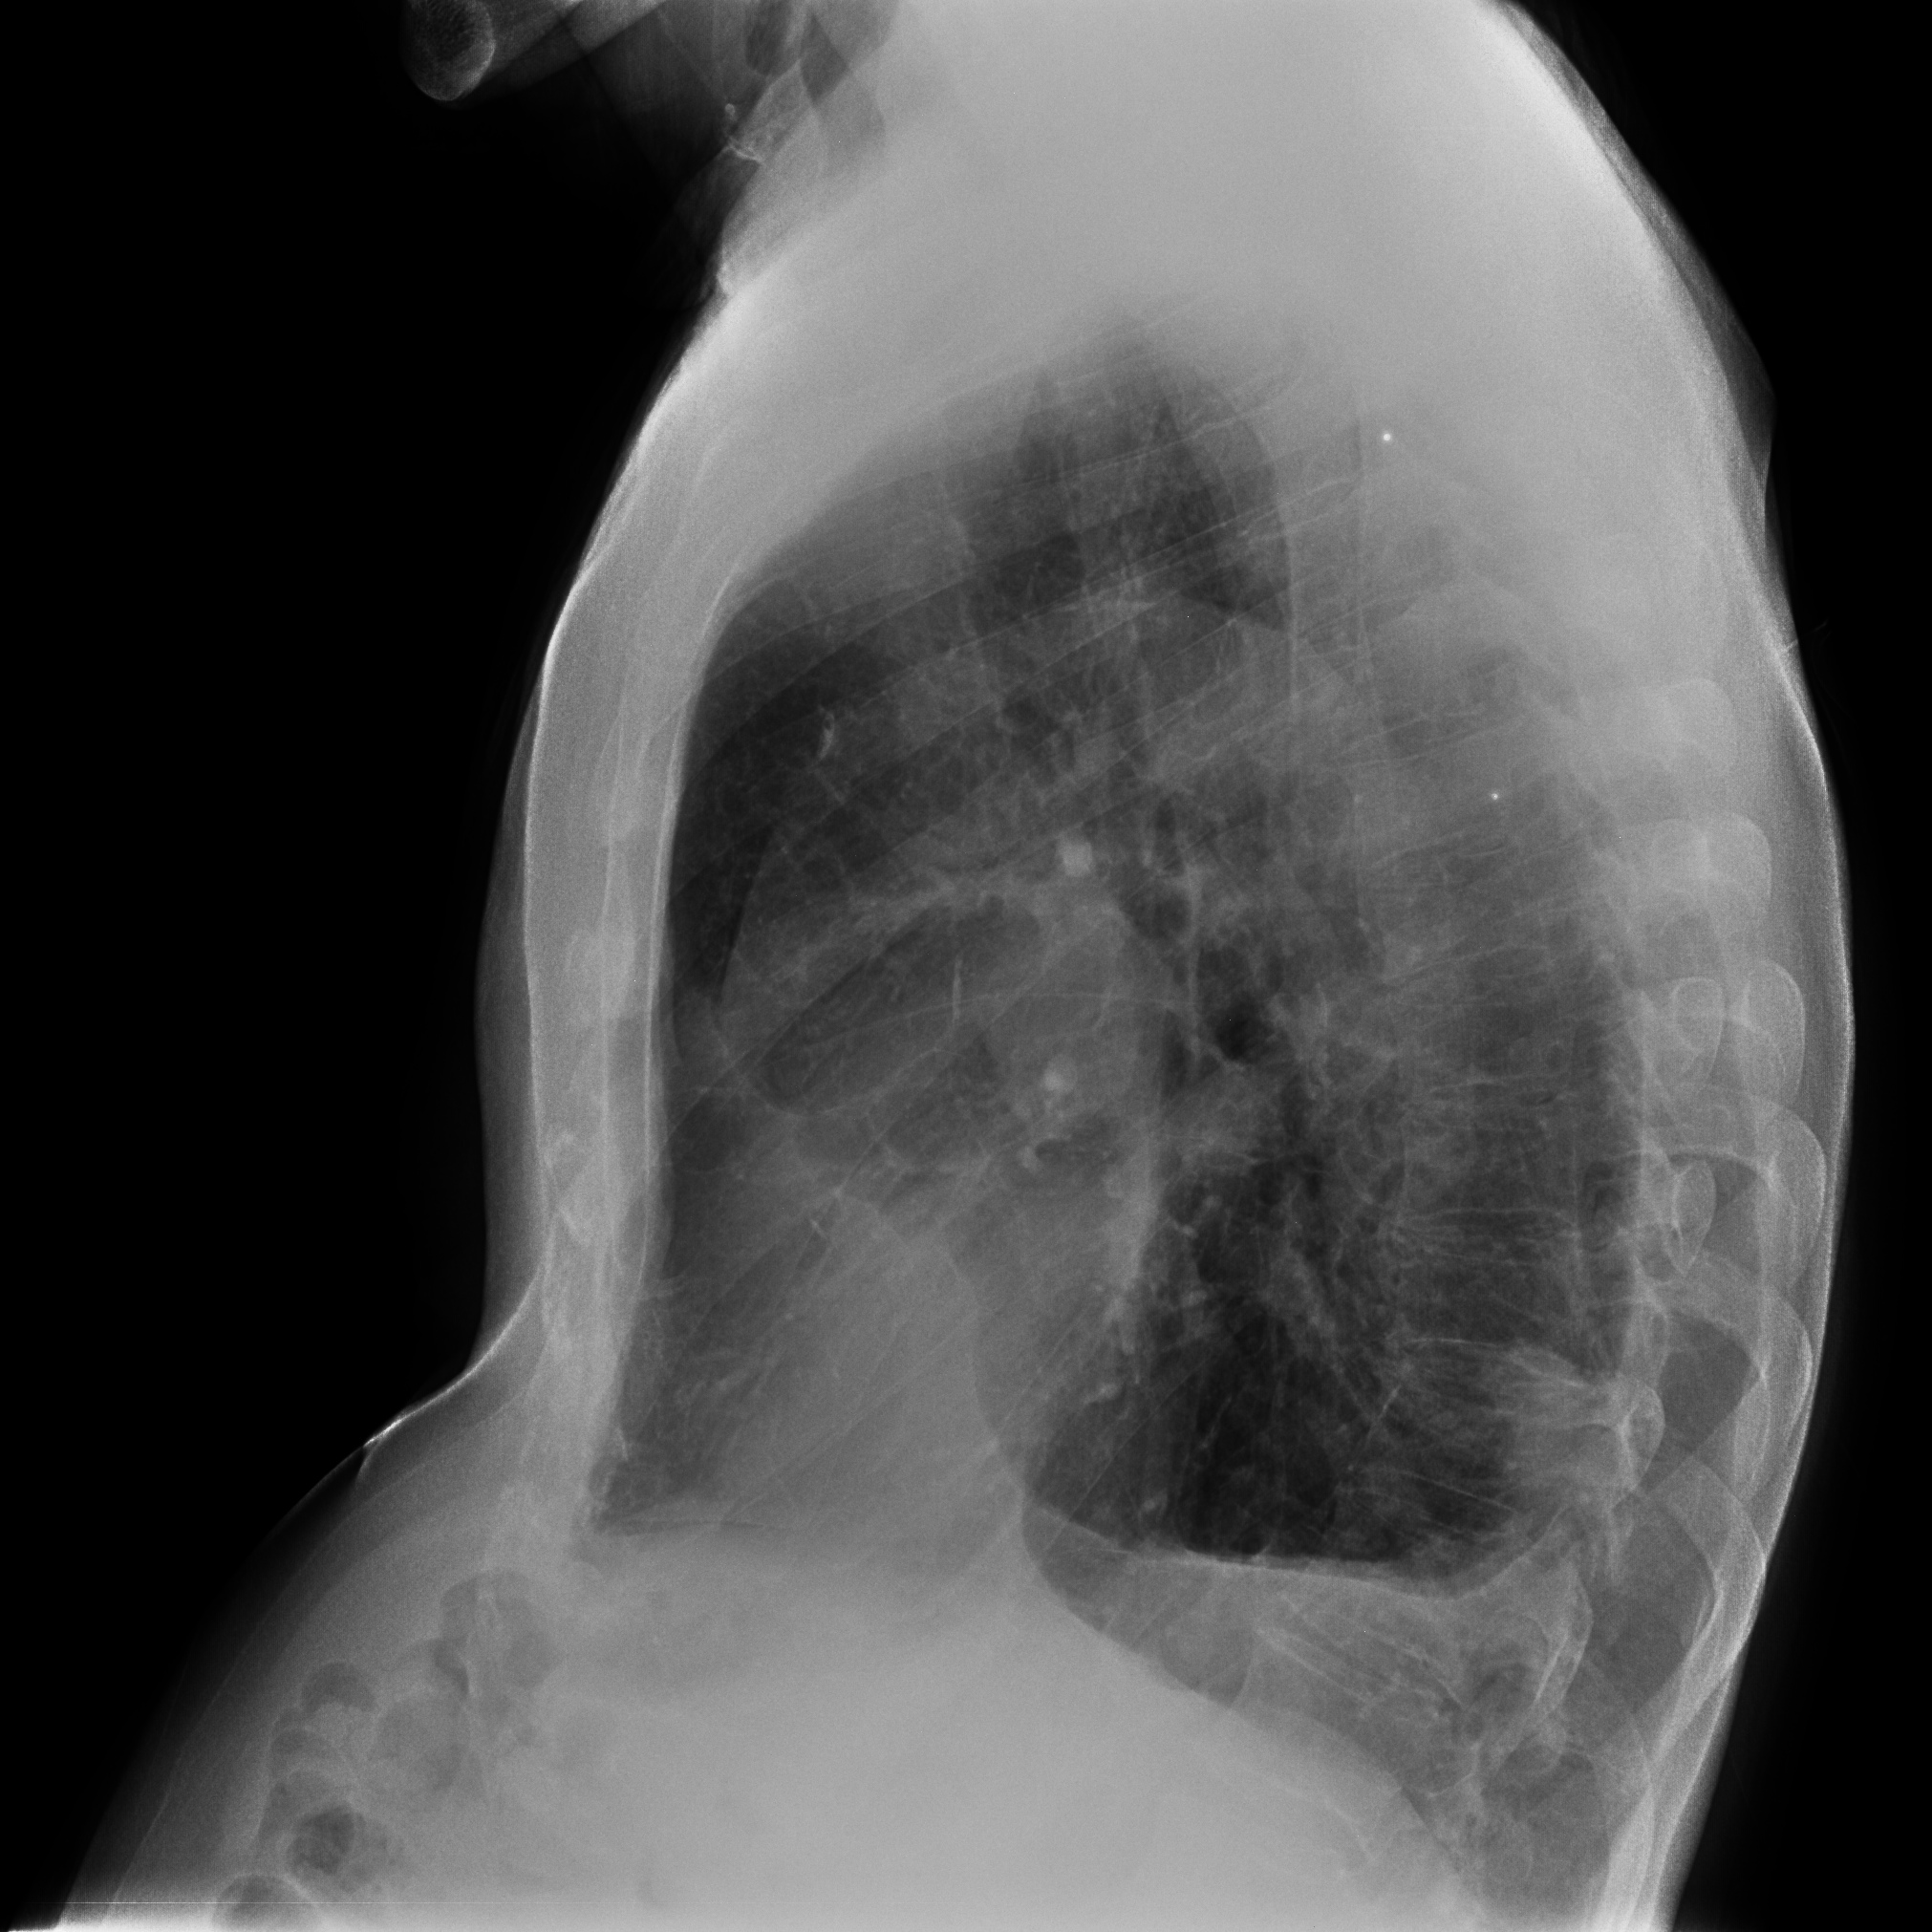

CASO: Febrícula y tos de 4 días de evolución.

Hallazgos:

- En la placa PA se observa una asimetría en los hilios pulmonares, el hilio izquierdo tiene una densidad aumentada.

- Tras examinar la placa lateral se observa un aumento de densidad en la columna que puede ser compatible con una condensación, es el signo de la desnificación vertebral.

SIGNO DE LA DENSIFICACIÓN VERTEBRAL: En la radiografía lateral normal, la densidad de la columna torácica tiende a disminuir desde la parte superior hasta el diafragma; la alteración de ese patrón por la presencia de una densidad superpuesta a la columna, indica la existencia de una consolidación pulmonar. Este signo adquiere especial valor cuando en la proyección posteroanterior la consolidación está oculta en el espacio retrocardíaco o en la base pulmonar.